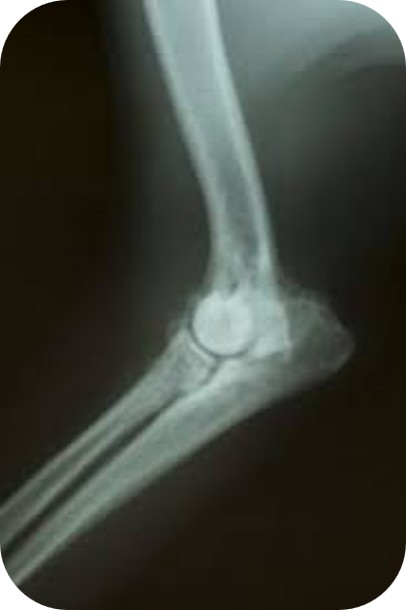

Arhrose Ellenbogen